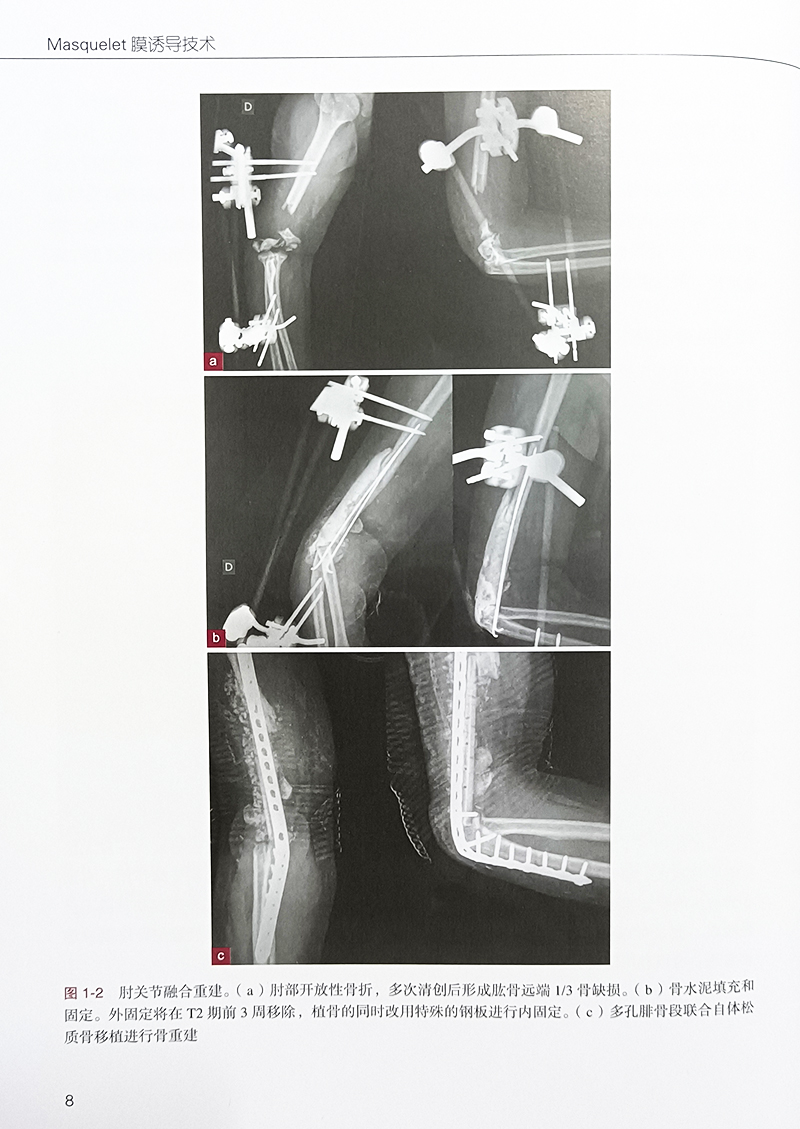

第 1 章 标准技术及衍生5